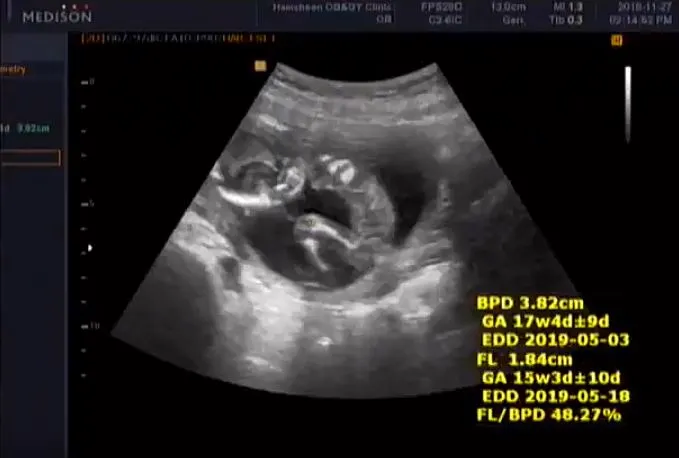

짠짠이 16주 차

16주.

점점 아기의 형태를 갖춰가는 짠짠이. 몸길이는 자기 주수와 비슷한데 머리는 1주 정도 더 크다(...). 표준 성장 주수가 서양 아기에 맞춰져 있어서 동양 아기는 몸이 짧고 머리가 더 크게 나오는 게 일반적이라고. 그게 무슨 상관이랴 건강하게만 자라면 되지 라고 생각은 했지만 그래도 짠짠이만 머리가 큰 게 아니라니 마음이 살짝 놓이는 게 솔직한 심정. 하지만 아빠가 머리가 크니 아마 마찬가지일 거야 짠짠아 미안. 그나저나 짠짠이 이 자식 다리 사이에 뭔가 있구나?!